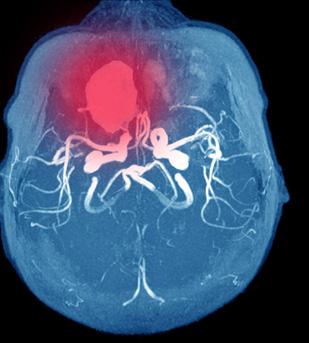

Figur 1. Frailty predikerer risiko for død på venteliste over MELD alene (9)